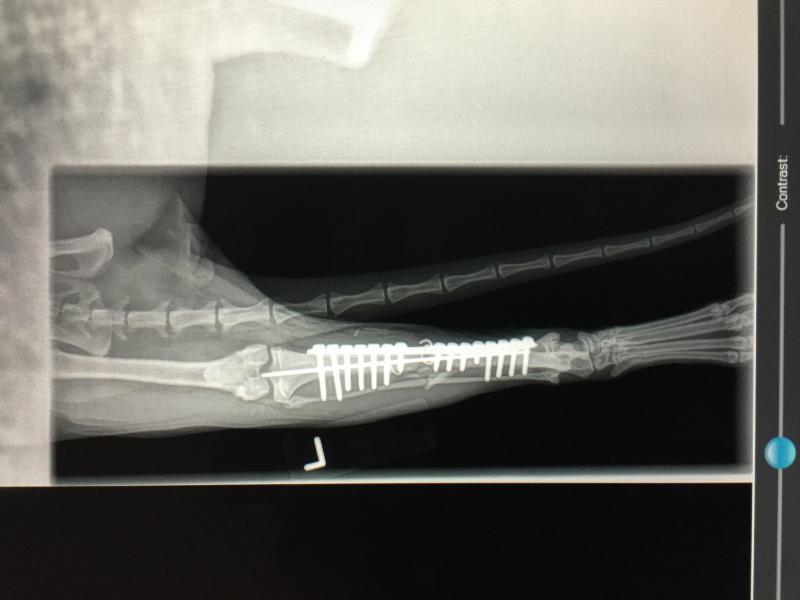

Hit by Car - 2 year old Labrador Retriever, External Fixator to repair transverse tibia/fibula break